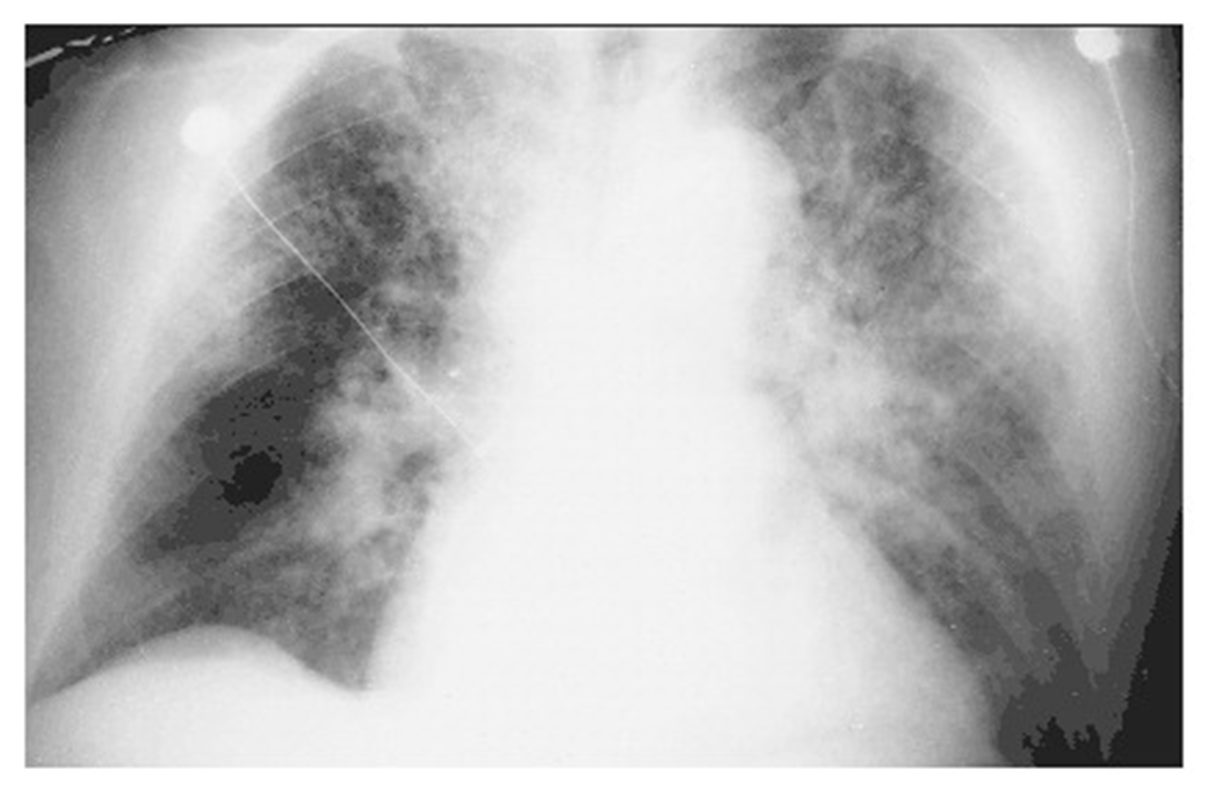

A 22-year-old woman whose blood culture was positive for Streptococcus pneumoniae, causing pneumonia complicated by septic shock and acute respiratory distress syndrome. Diffuse alveolar infiltrates appear patchy and bilateral with air bronchograms

alveolar flooding leads to arterial hypoxemia and may be associated with cough and expectoration of frothy edema fluid

what is the most likely cause of increased permeability?

D